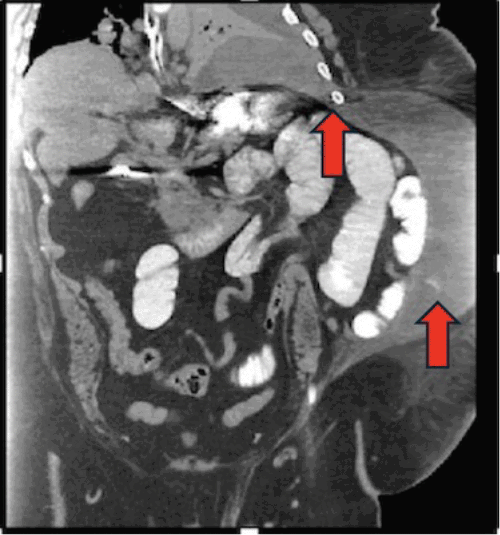

The patient was initially managed conservatively with bowel rest, intravenous hydration, and electrolyte repletion, targeting standard resuscitation parameters (mean arterial pressure >65 mmHg, heart rate <120 bpm, urine output ≥0.5 mL/kg/hr, capillary refill <2 seconds, and normalization of BUN, creatinine, electrolytes, and lactate). A nasogastric tube was placed for decompression, and intravenous analgesia was administered judiciously, avoiding narcotics where possible. Serial laboratory evaluations and physical examinations were performed to monitor for signs of worsening systemic inflammatory response, metabolic acidosis, increasing abdominal distension, or the development of peritonitis. Despite these measures, on hospital day five, the patient experienced a significant clinical deterioration, manifesting as sepsis and acute respiratory failure. A repeat CT scan at this time demonstrated a new, large, loculated, mixed-density pleural effusion on the left side (Figure 2). Crucially, this scan provided complete visualization of the hernia sac, revealing a persistent small bowel obstruction and a new extraperitoneal fluid collection within the abdominal wall, which appeared to be tracking superiorly into the pleural cavity (Figure 3).

Figure 3. CT Demonstrating Extraperitoneal Bowel Perforation and Pleuro-Abdominal Communication. Published with Permission

Image shows extraperitoneal collection of fluid and gas within the left abdominal wall (arrow), consistent with bowel perforation within the hernia sac. Note the evidence of contrast extravasation and a communicating tract (arrow) extending from this collection superiorly towards the left pleural cavity

Given these findings, the patient was taken emergently to the operating room. A left-sided Wayne pigtail catheter was initially placed into the pleural space for decompression, yielding an immediate return of approximately 3,000 mL of succus entericus (Figure 4A), confirming a pleural effusion entericus. Correct intrapleural placement of the catheter was verified. Subsequently, the hernia sac was explored via a left flank incision. This revealed a 5 cm rupture of the hernia sac containing a strangulated and perforated loop of small bowel. Enteric contents were observed draining from this perforation into the abdominal wall planes and tracking superiorly through fascial defects into the pleural space (Figure 4B). The necrotic segment of small bowel was resected, and intestinal continuity was restored with a stapled anastomosis; the repaired bowel was then returned to the peritoneal cavity. A diagnostic laparoscopy was performed, which confirmed the absence of any primary diaphragmatic defect, further intraperitoneal bowel ischemia, or gross peritoneal contamination. Further exploration of the abdominal wall revealed that the chronic, large left flank hernia had significantly distorted the normal anatomical planes, including the fascial and muscular connections with the diaphragm and chest wall. This distorted anatomy likely facilitated the upward tracking of the succus entericus from the extraperitoneal perforation along the path of least resistance into the pleural space, as depicted on the CT images (Figure 3). This abnormal abdominal wall-to-pleural communication was also visualized thoracoscopically using a 30-degree scope.